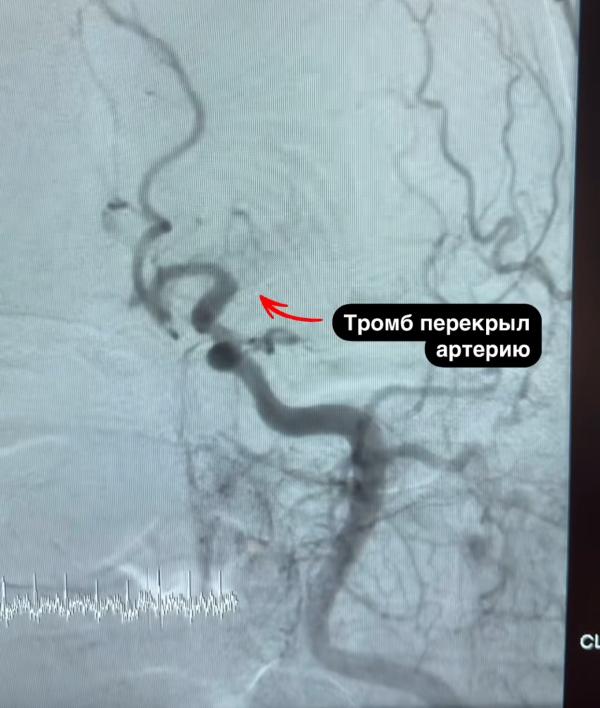

Я в школе училась с парнем, сейчас он известный областной кардио хирург. И блогер)) так вот он очень подробно и наглядно рассказывает про операции при инсульте, как на рентгене выглядят тромбы, Как их удаляют.

И в общем для такой операции используется тонкая сеточка. Ее стоимость что-то то ли 150 то ли 200 тысяч, и она одноразовая. Но людям эти операции делают разумеется бесплатно, лично он на дежурстве по 3-4 сеточки в ДЕНЬ использует. Огромные деньги..